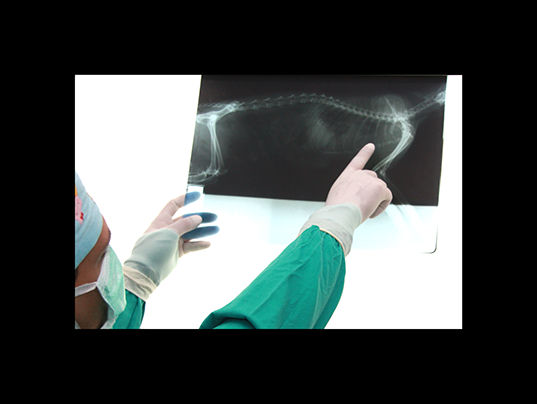

traumatología

En clinican podemos tratar las diversas afecciones que pudan afectar a huesos y articulaciones

radiología

La radiologia es imprescindible en traumatologia y en algunos diagnosticos, ya sea mediante radiologia simple ó de contraste.